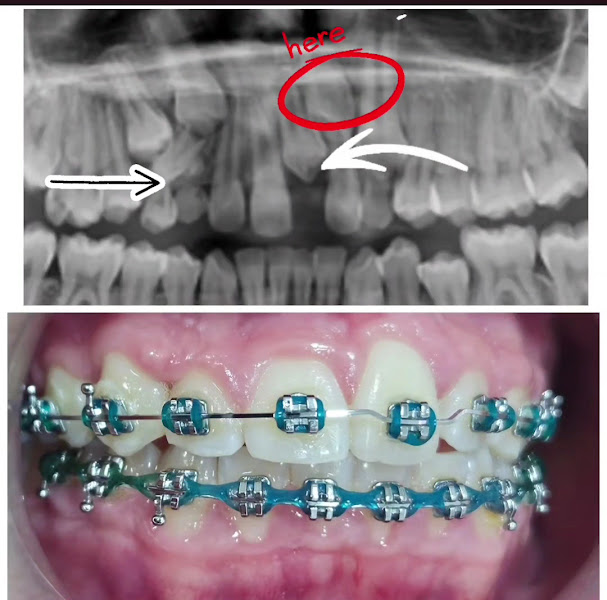

Fotos

Conheci o trabalho do Dr. Paulo Pires e posso afirmar que é um excelente profissional! Muito competente em ortodontia e harmonização. Atencioso com os pacientes e o melhor: atendimento rápido e eficiente. Pode confiar no trabalho dele. Faz toda a diferença ser atendido por alguém que realmente se preocupa com o paciente e entrega um serviço de qualidade! Super indico!